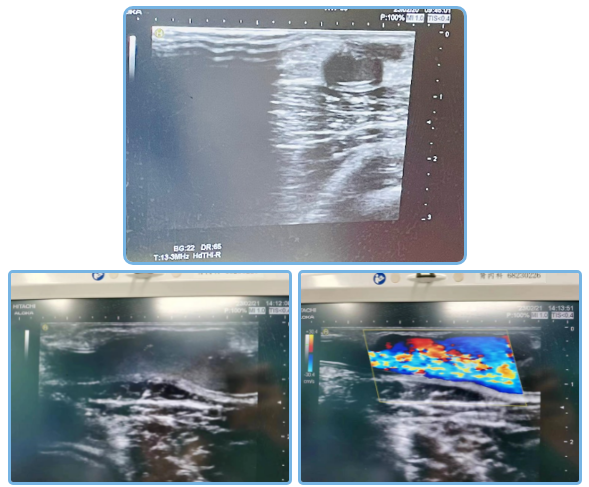

慌张的他在别人的介绍下,来到了广医五院肾内科就诊。检查发现,陈叔的左前臂AVG可触及血管震颤,可闻及血管杂音,近肘关节处可见一直径大小约75px的瘤样扩张。血管B超提示,移植物动静脉内瘘见假性动脉瘤形成。考虑到陈叔的假性动脉瘤是因为人工血管破裂形成,破口长达2公分,宽近0.5公分,存在较高的感染及破裂出血风险,需要尽快接受手术治疗,拆掉这个“不定时炸弹”。

修补后AVG未见震颤,超声检查示人工血管内血栓形成,使用尿激酶40万u人工血管管腔内注射溶栓,溶栓后AVG可触及震颤,超声检查见血流信号可。